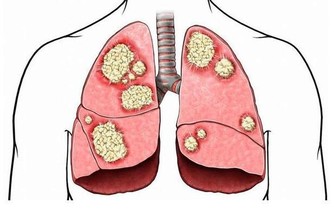

4、鵝口瘡

嘴上長泡,暗藏6種致命疾病,做對5件事清火排毒!

由真菌感染引起的白色斑塊,猶如雪花層層疊疊,多發於頰舌、軟齶及口唇部的粘膜上,嬰幼兒最易受感染。例如,奶瓶奶嘴消毒不徹底,孩子愛咬手指,母乳喂養時,媽媽的乳頭不清潔都是感染源。

另外,長期服用抗生素類藥物的老年人也容易得。患病後最好去醫院做口腔全面檢查。